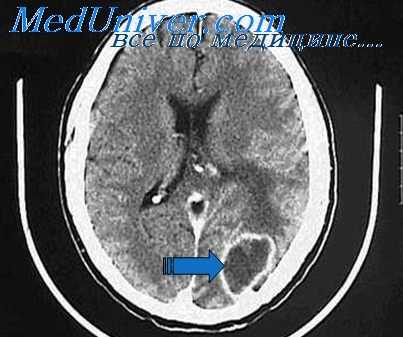

Абсцесс левого полушария мозжечка и расширение боковых желудочков, выявленные при магнитно-резонансной томографии головного мозга в T1 C+ режиме на коронарном срезе.